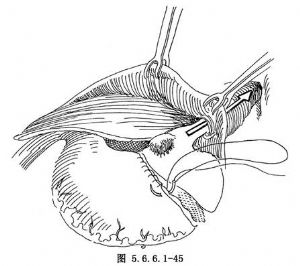

(4)距肿瘤下缘约5cm用自动胃肠缝合器(GIA)缝合、横断胃(图5.6.6.1-44)。用一把Kocher钳夹住胃之上切缘,而将下切缘再用中号线连续缝合加固,并用细丝线间断浆肌层缝合法包埋之(图5.6.6.1-45)。